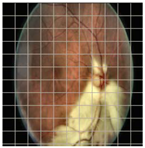

3.2. Models Explainability on the Test Set

| Original Image | VGG16 | ResNet-18 | DenseNet-121 |

|---|---|---|---|

![]() | ![]() | ![]() | ![]() |

| (a) | |||

| (b) | |||

| (c) | |||

| (d) | |||